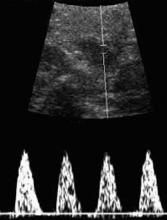

Sequential pneumatic compression devices

Like GCS, these devices decrease the caliber of veins by simple compression. They also increase blood flow velocity and stimulate the endogenous fibrinolytic system.

Enhanced fibrinolytic activity due to intermittent compression occurs even if the device is used on only 1 lower extremity, or on an upper extremity. Patient and nursing-staff compliance may affect efficacy. Sequential pneumatic compression devices (SPCDs) may be thought inconvenient, impeding nursing functions. Some patients may find the repetitive inflation-deflation cycles annoying.

These devices must be activated prior to surgery and continued for a minimum of 24 hours. Some studies suggest that SPCDs be used for 5 days in high-risk situations.16

Calf- and thigh-length devices have similar effects. Rare complications include peroneal nerve injury and compartment syndrome.

What the data show. In an analysis of 4 trials comparing SPCDs with no therapy, thromboembolic disease occurred in only 2% of patients who wore SPCDs but in 20% of those who did not.17 Compared with low-dose unfractionated heparin, no difference in the rate of DVT was seen.18 However, risk of transfusion and retroperitoneal drainage volume increased in the heparin group.